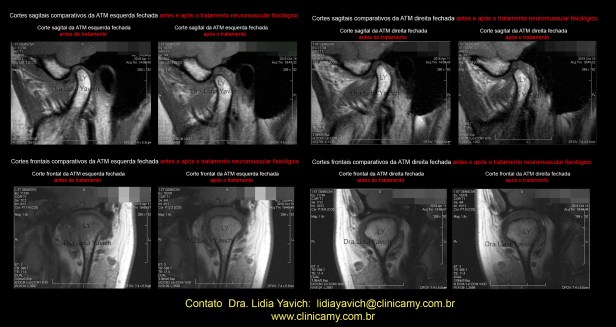

RNM: Comparação do corte sagital da ATM esquerda, boca fechada, antes do tratamento neuromuscular fisiológico, e da mesma ATM esquerda, boca fechada, após A PRIMEIRA FASE do tratamento.

Recuperação da relação fisiológica da cabeça da mandíbula com o disco articular.

RNM: Comparação do corte sagital da ATM direita, boca fechada, antes do tratamento neuromuscular fisiológico, e da mesma ATM direita, boca fechada, após A PRIMEIRA FASE do tratamento.

RNM: Comparação do corte FRONTAL da ATM ESQUERDA, boca fechada, antes do tratamento neuromuscular fisiológico, e da mesma ATM ESQUERDA, boca fechada após a FINALIZAÇÃO DA PRIMEIRA FASE do tratamento.

RNM: Comparação do corte FRONTAL da ATM direita, boca fechada, antes do tratamento neuromuscular fisiológico, e da mesma ATM direita, boca fechada após a FINALIZAÇÃO DA PRIMEIRA FASE do tratamento.

A paciente não relatou mais sintomatologia. A RNM comparativa mostrou a Recuperação da relação fisiológica da cabeça da mandíbula com o disco articular.